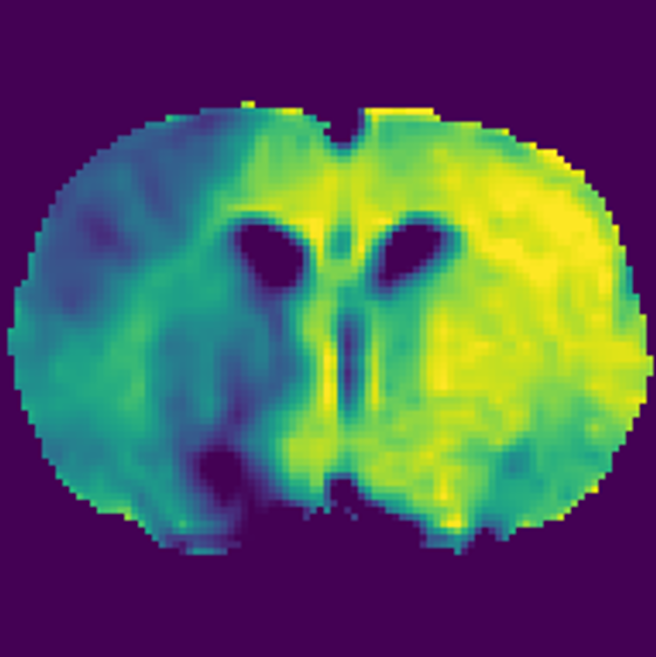

Image Attribution

Protocol title image is reproduced under a CC-BY license from Boehm-Sturm P, Schuenke P, Foddis M, Mueller S, Koch SP, Beard DJ, Holloway P, Mottahedin A, Schröder L, Buchan AM, Mergenthaler P. Open Data Repository - 2-deoxy-D-glucose chemical exchange-sensitive spin-lock MRI of cerebral metabolism after stroke in the rat. Zenodo. [Data set] doi: 10.5281/zenodo.14526091. https://doi.org/10.5281/zenodo.14526091.